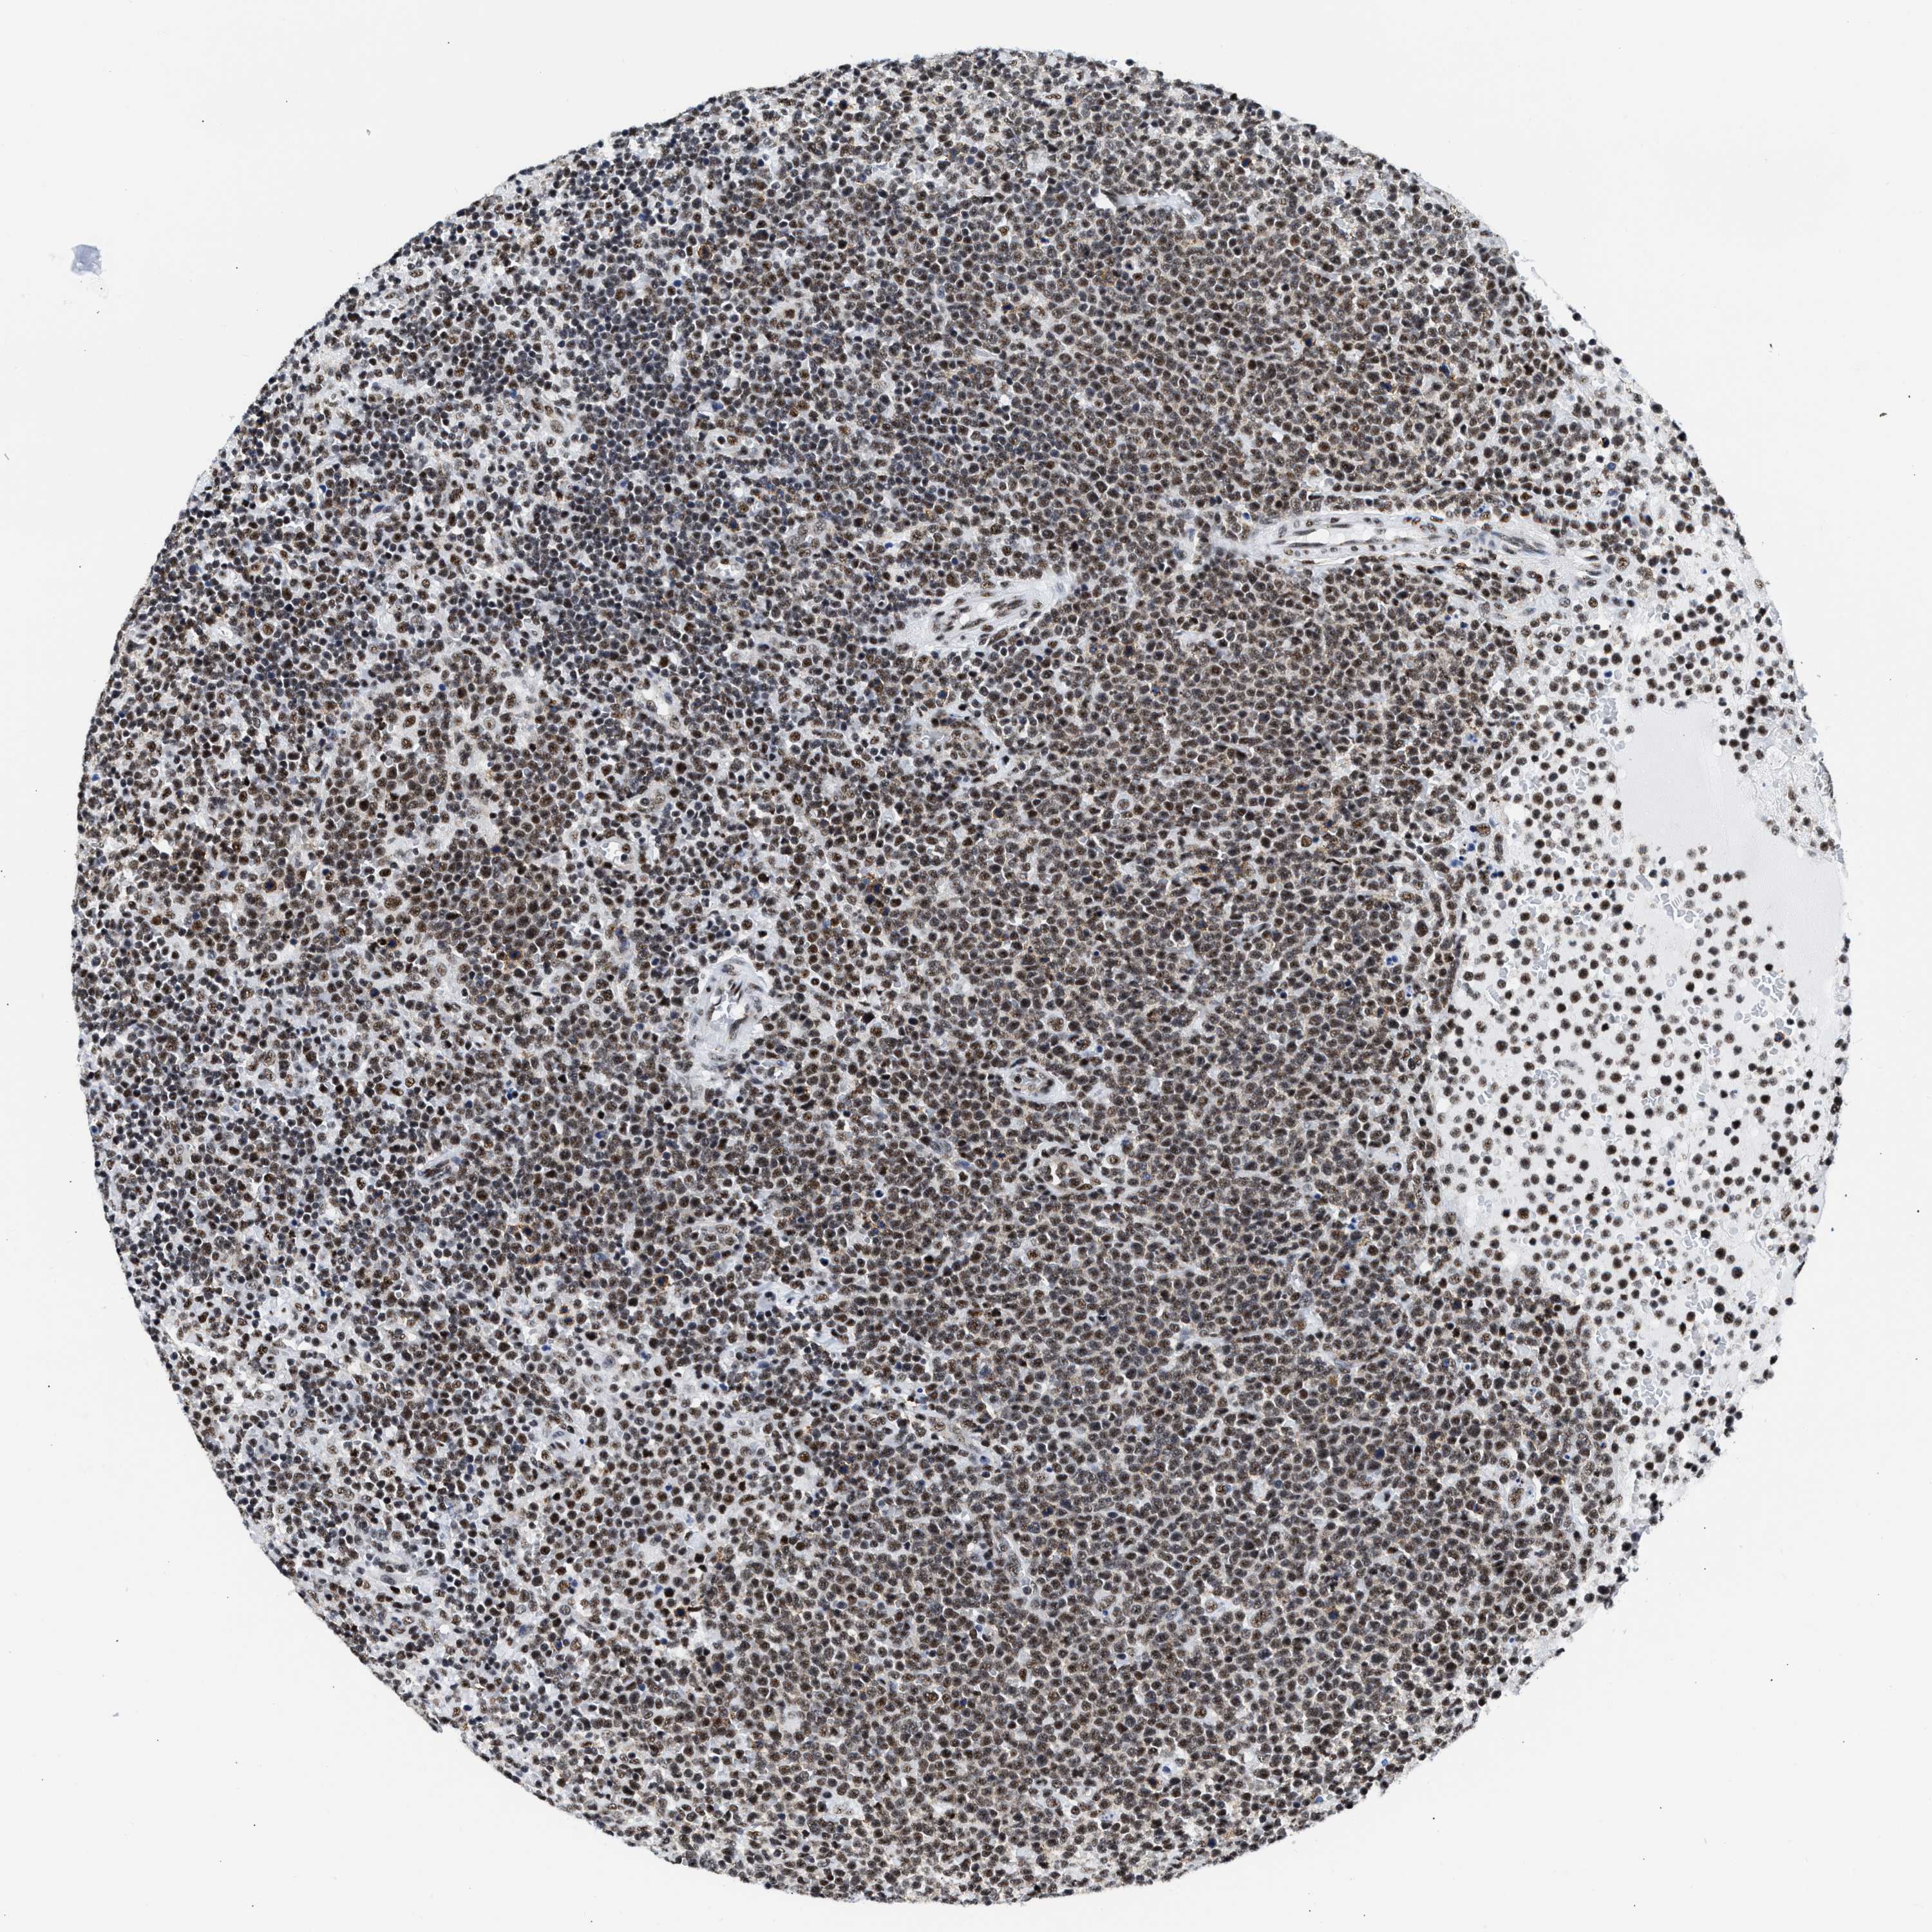

CANCER LYMPHOMA Show tissue menu

LYMPHOMA - Protein expressioni

A mouse-over function shows sample information and annotation data. Click on an image to view it in a full screen mode. Samples can be filtered based on level of antibody staining by selecting one or several of the following categories: high, medium, low and not detected. The assay and annotation is described here.

Antibody stainingi

Antibody staining in the annotated cell types in the current human tissue is reported as not detected, low, medium, or high, based on conventional immunohistochemistry profiling in selected tissues. This score is based on the combination of the staining intensity and fraction of stained cells.

Each image is clickable and will lead to virtual microscopy that enables deeper exploration of all samples and also displays staining intensity scores, fraction scores and subcellular localization as well as patient and tissue information for each sample.

Antibody HPA018403

Staining

High

Intensity

Strong

Quantity

>75%

Location

Nuclear

Hodgkin's disease, NOS

Malignant lymphoma, non-Hodgkin's type, High grade

Malignant lymphoma, non-Hodgkin's type, Low grade